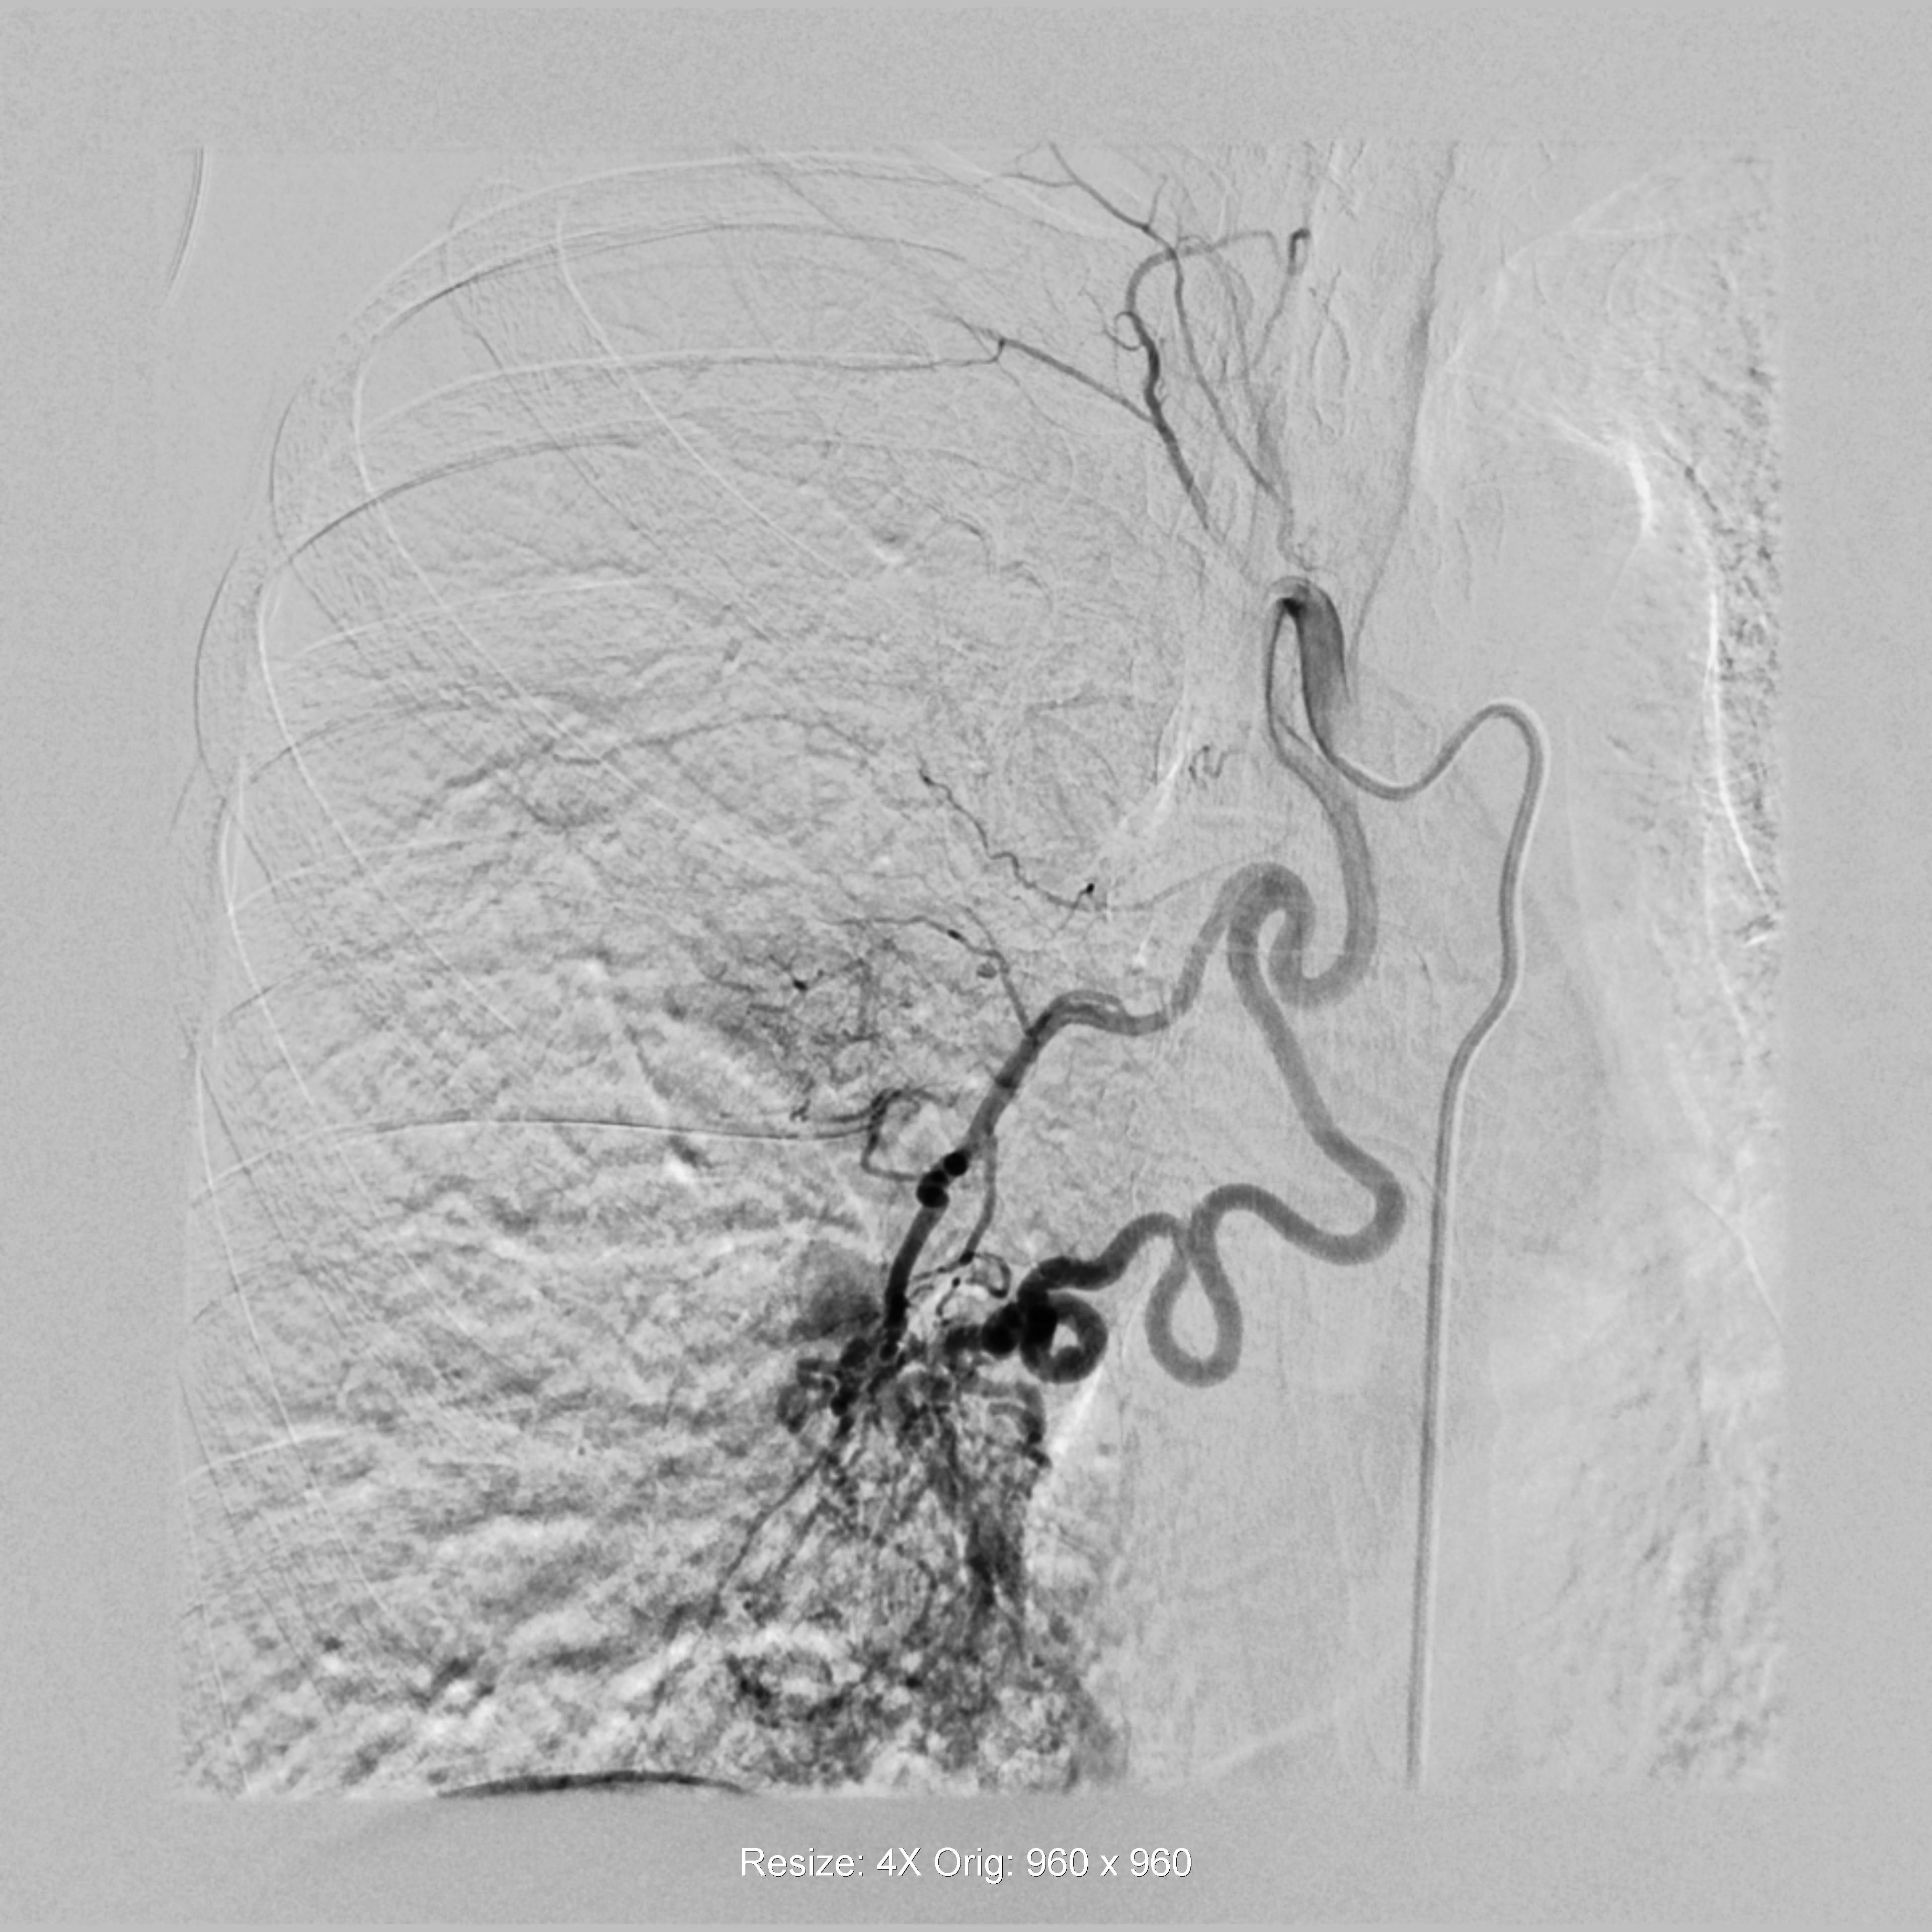

术前造影(R)

“能不能少遭点罪?”面对家属的恳求,医院介入导管室医护团队决定启用新技术。通过术前CTA与术中DSA影像精准配准,借助3D Fusion技术让迂曲血管立体呈现,再利用Overlay技术将血管走形叠加在实时画面上,原本难以定位的出血点被“一眼锁定”。微导管在导航引导下快速精准到达靶血管,注入栓塞剂后成功止血。从麻醉到手术结束,全程仅用45分钟,较传统手术缩短近2小时。